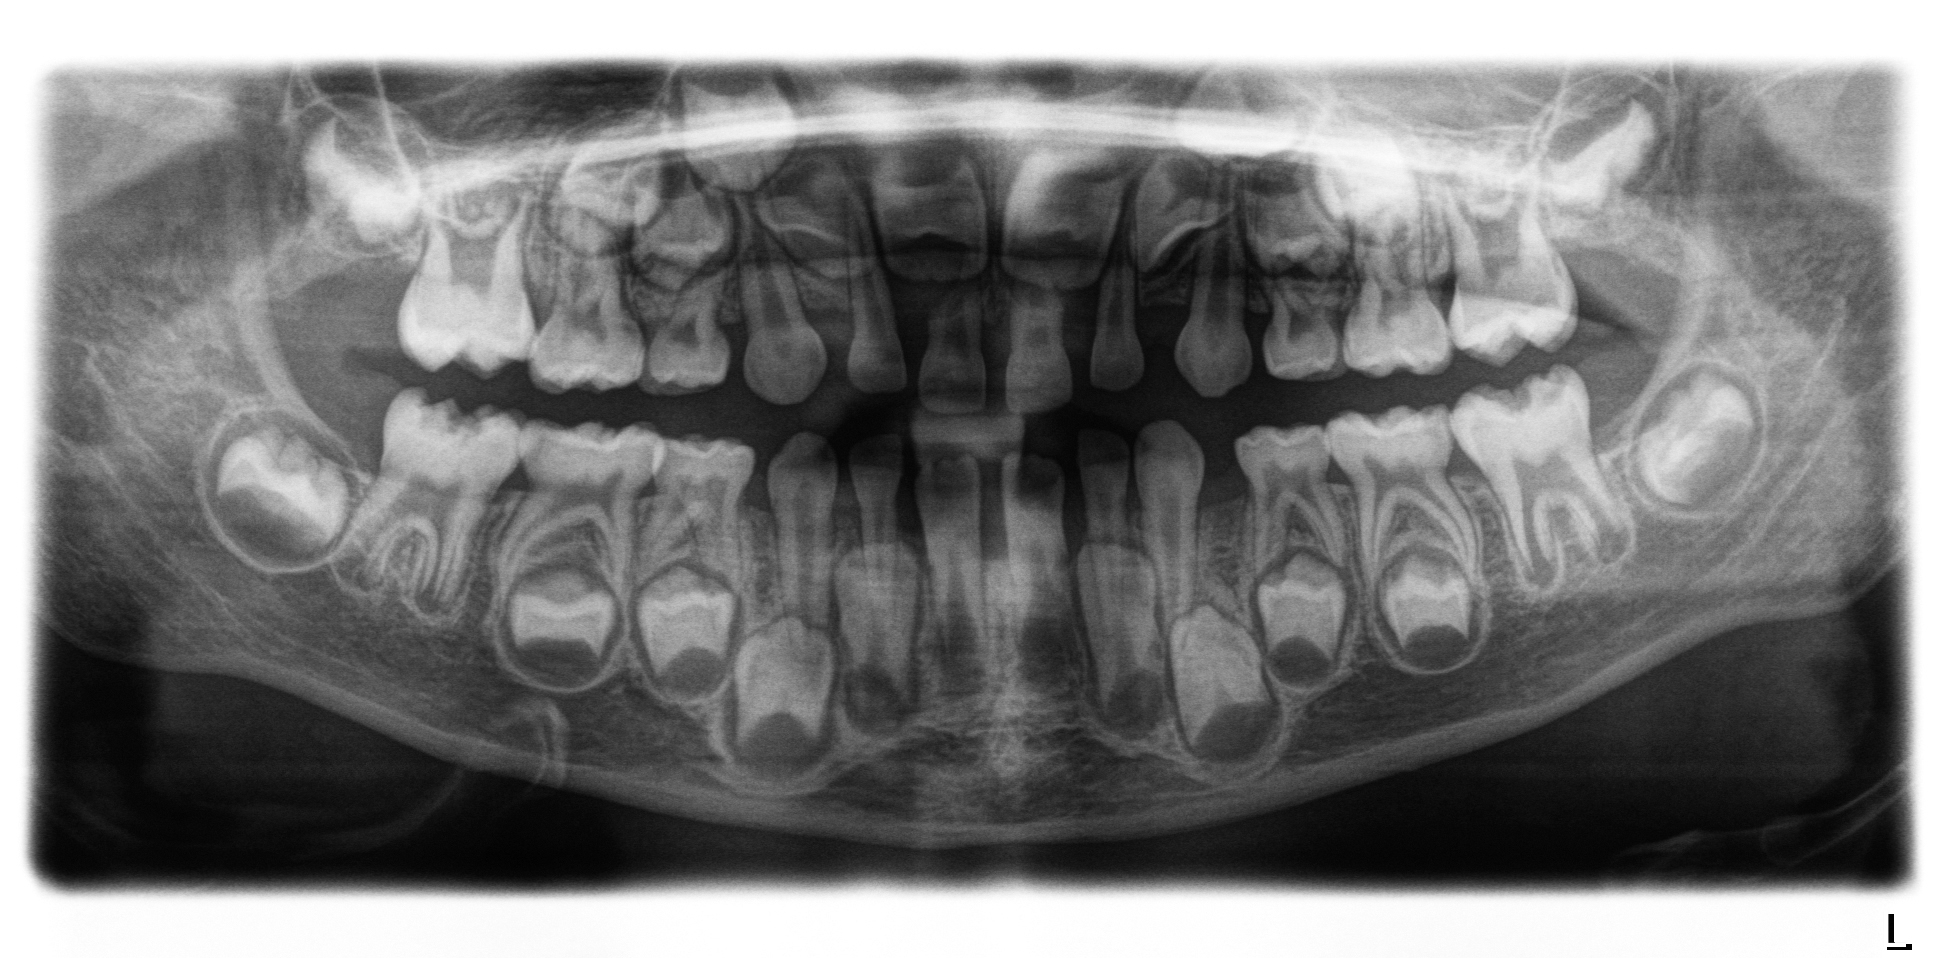

Allerdings sollte vor der geplanten Extraktion eines Sechsjahrmolaren eine radiologische und kieferorthopädische Beurteilung der Gebisssituation erfolgen [Brusevold et al., 2022], um die Anlage der bleibenden Zahnkeime zu überprüfen und mögliche Dysgnathien zu diagnostizieren [Ashley and Noar, 2019]. Zusätzlich sollte der optimale Zeitpunkt für eine geplante Extraktion gewählt werden [Lygidakis et al., 2022].

Auch wenn ein Alter von acht bis zehn Jahren als geeigneter Zeitpunkt für die Extraktion eines Sechsjahrmolaren gilt, ist der spontane Lückenschluss nicht immer gewährleistet [Ashley und Noar, 2019]. Insbesondere bei der Extraktion von Sechsjahrmolaren im Unterkiefer gilt der spontane Lückenschluss als weniger wahrscheinlich als im Oberkiefer [Brusevold et al., 2022].